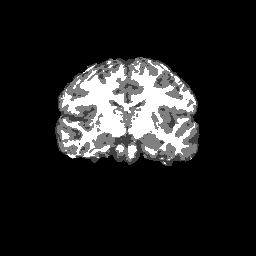

Test/Retest Reliability

FSL was run on each scan in the Brain Segmentation Testing Protocol (BSTP) between-scanner test/retest dataset. Select a subject below to see volumes for each subject across the subject's scans.